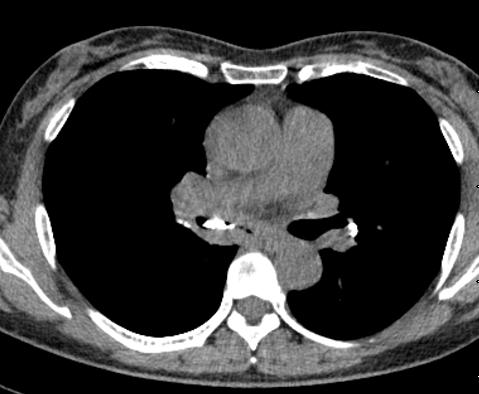

图10~图15 胸部CT示双肺多发钙化灶

问题出在哪儿?

右中间支气管的钙化病灶向外移动,钙化病灶的尖端刺激到支气管粘膜了(图16)。

另外,这个患者的钙化灶非常危险,因为钙化灶的一端距离肺动脉才2毫米左右(图17),支气管镜下强行牵拉钙化病灶很可能会大出血危及生命。